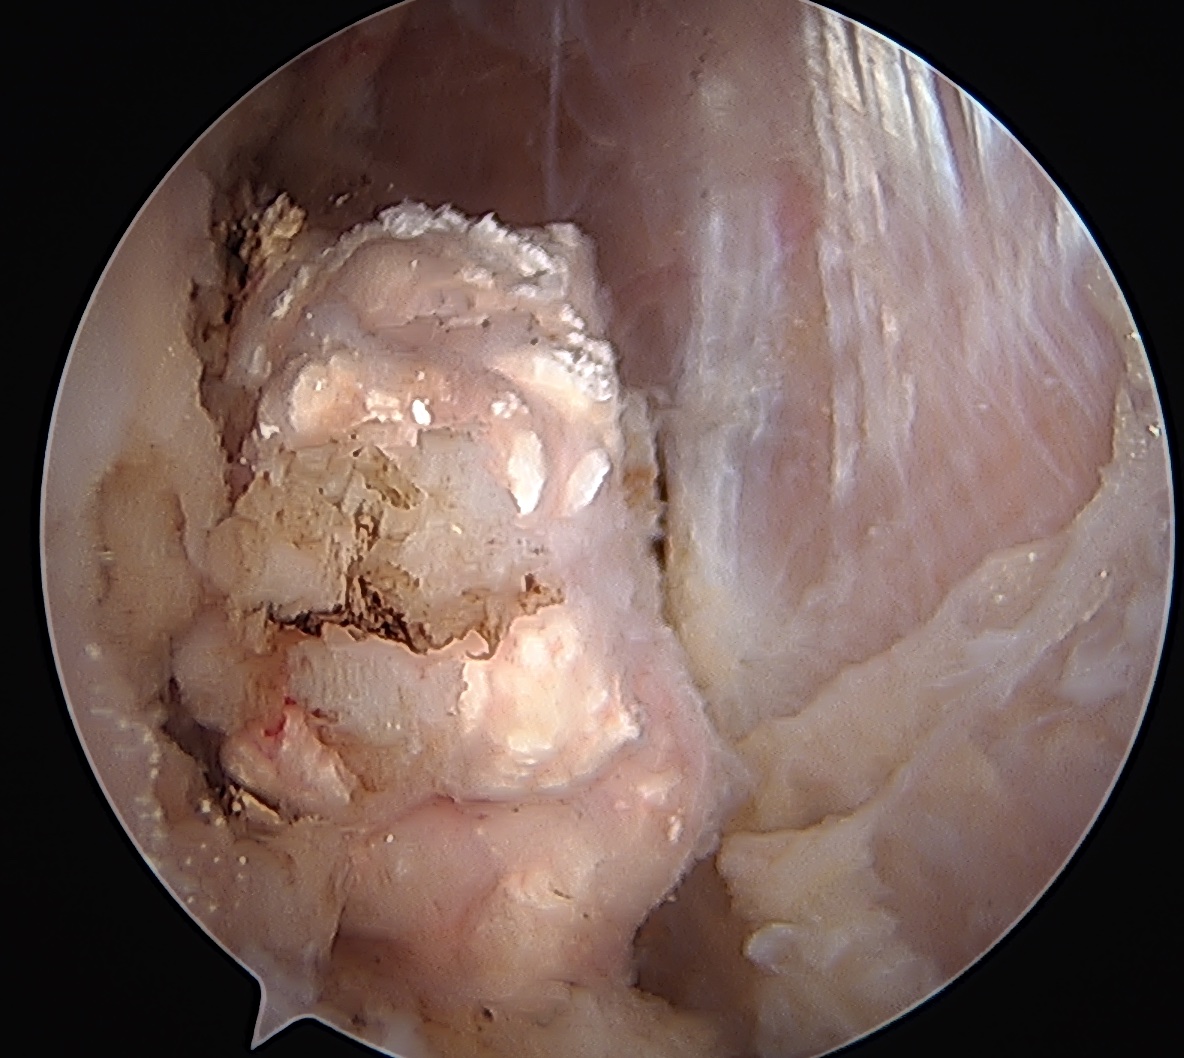

Arthroscopy